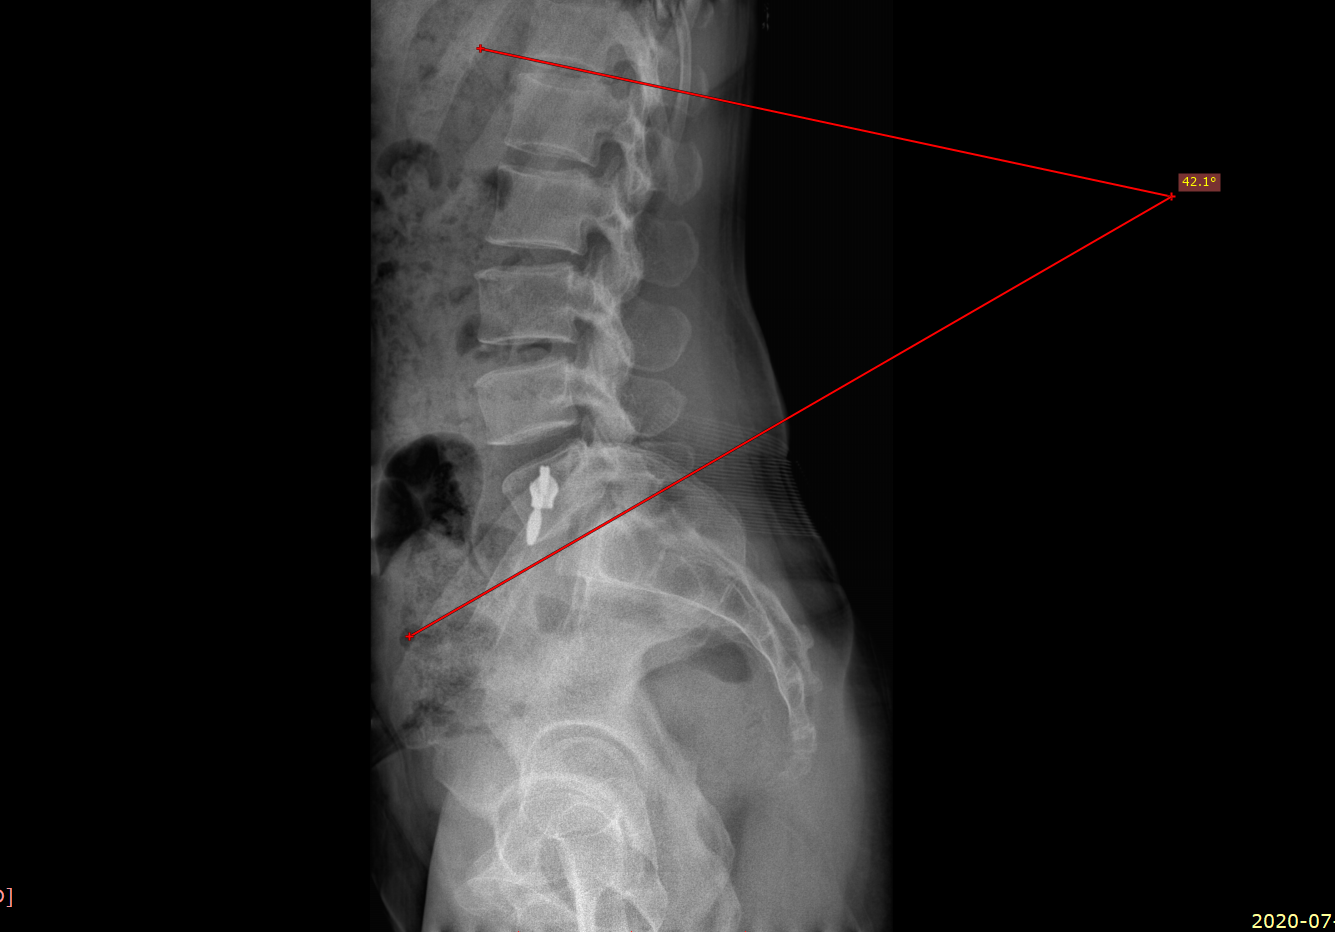

골반 전방 경사 되면, 요추는 과전만 된다고....

그리고, 군의관으로 사단 의무대 근무 당시 정말 열심히 엑스레이 찍어서 확인해 봤는데...

왠 걸, 안 맞더라구요....

사람 몸이 제각각이고 좌우 대칭이 안 된다는 걸, 교과서적으로 맞질 않다는 걸 아주 절실히 봤습니다.

치료에 있어서도 반드시 확인해 봐야 할 부분입니다.

추나 치료나 스트레칭, 도수 치료 등을 시행하시는 분들은 꼭 사진 촬영을 통해서 확인을 해 보세요.

눈으로 보는 것과는 확연히 다릅니다.